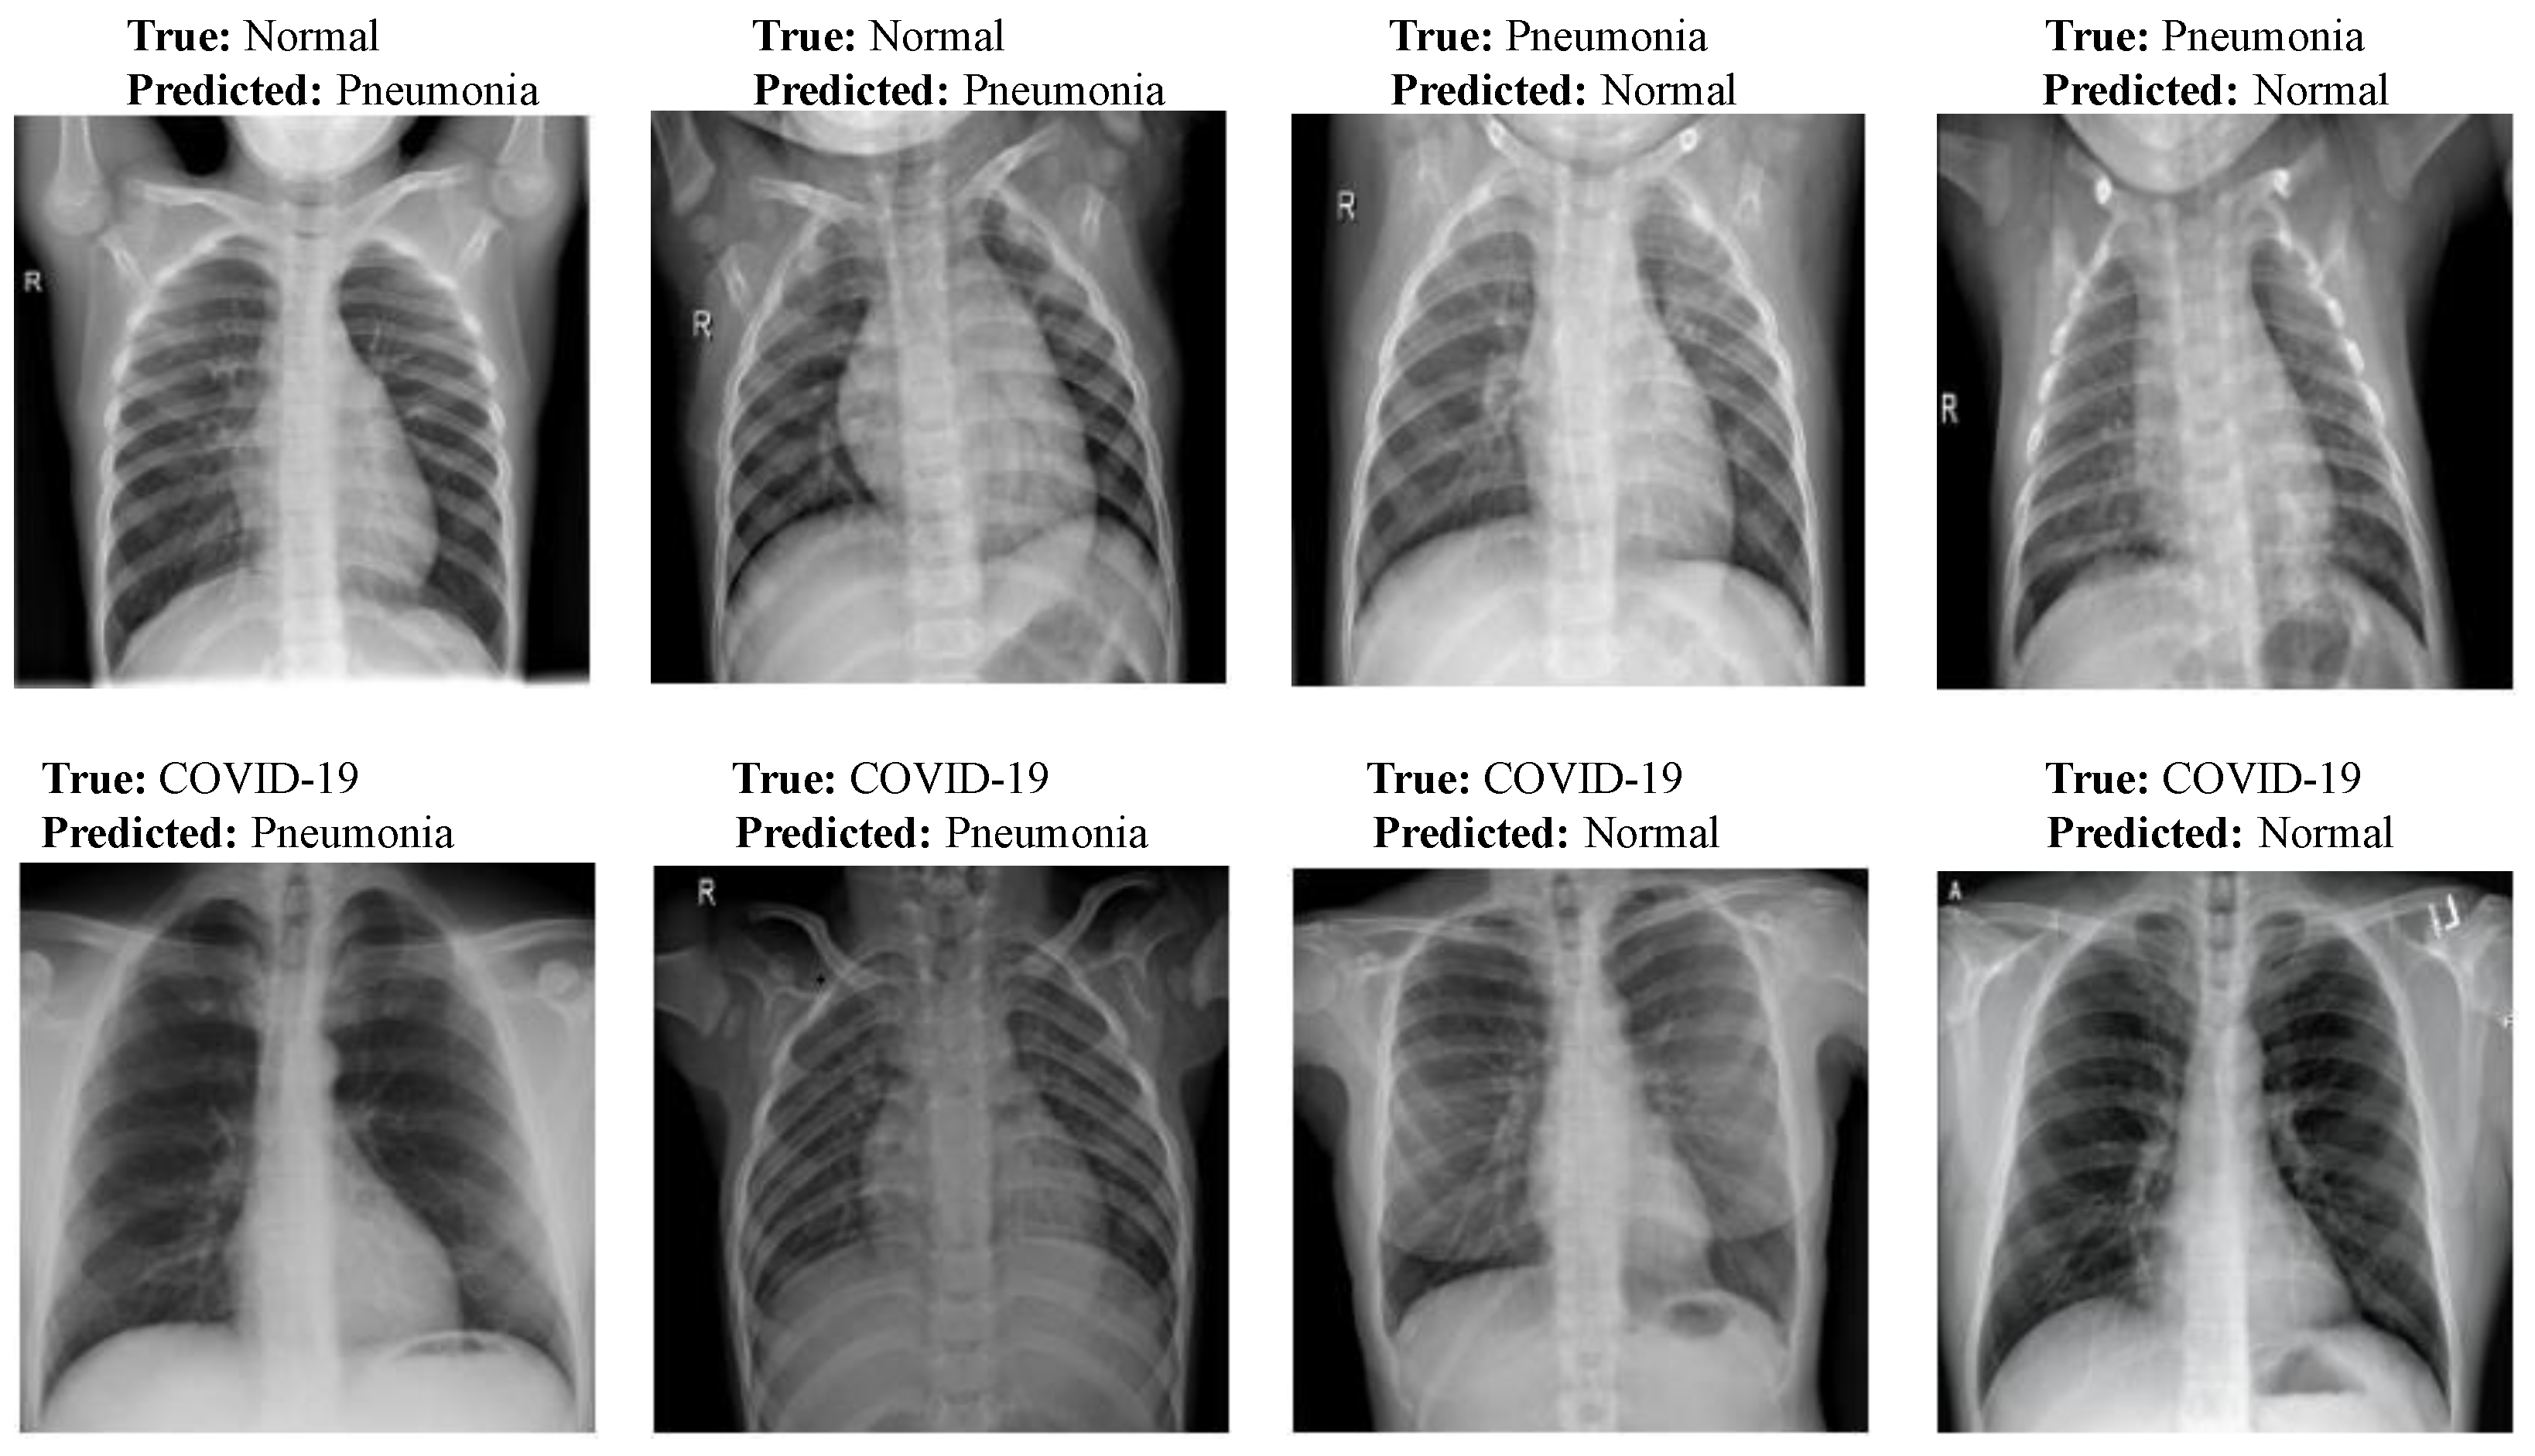

3.3. Misclassification Results Analysis

Figure 13 shows few misclassification results yielded by LW-CORONet on Dataset-1. These errors possibly occurred because of the similar visual features among the CXR images of the three classes.

Figure 13.

Sample misclassification outcomes of LW-CORONet.